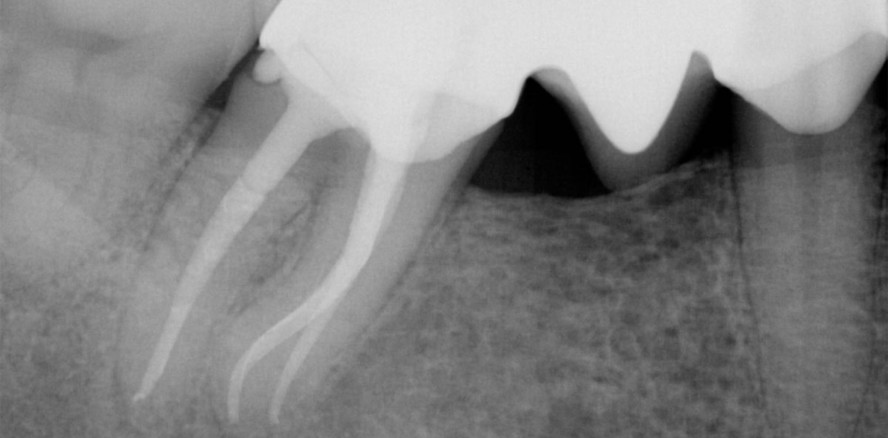

Der extraorale Befund war unauffällig. Intraoral imponierte eine vestibuläre Fistel, die bei aktiver Manipulation zum Pusaustritt führte. Die Brücke wirkte bei der klinischen Sondierung suffizient. Die Trepanationsöffnung war mit einem provisorischen Material verschlossen. Die ursprüngliche Schmerzsymptomatik war vollständig rückläufig. Die Sondierungstiefen überschritten 4 mm nicht. Röntgenologisch zeigte sich in der Eingangsaufnahme (Abb. 1) eine ausgedehnte apikale Osteolyse, die mesial die Form eines J-Schattens einnahm und sich distal auf den apikalen Bereich begrenzte. Ein frakturiertes Instrument konnte im mittleren Wurzeldrittel der mesialen Wurzel lokalisiert werden. Distal zeigte sich eine unvollständig in den Kronenrand einbezogene präprothetische Aufbaufüllung. Gemäß den Richtlinien der AAA wurden folgende Diagnosen gestellt: asymptomatische apikale Parodontitis und nach initialer Wurzelkanalbehandlung, chronischem Abszess und Instrumentenfragment 46. Differenzialdiagnostisch empfiehlt es sich gerade bei J-förmiger Struktur, bei der Aufhellung sehr akribisch und ggf. unter lokaler Anästhesie eine forcierte engmaschige Sondierung des Sulkus vorzunehmen. Häufig ist diese Form der Aufhellung mit vertikalen Wurzelfrakturen assoziiert, die klinisch durch solitäre Knochentaschen imponieren.

Die Aufbereitung erfolgte in reziprokierender Arbeitsweise mittels der R25 blue (VDW) in der Crown-Down-Technik mit den typischen 2 bis 3 Picks bis zum Erreichen der Arbeitslänge. Nach jedem maschinellen Feileneinsatz wurde schallgestützt aktiviert und rekapituliert. Die apikale Erweiterung wurde in Abhängigkeit von der Farbe des entfernten Debris bestimmt. Die apikale Vergrößerung in den beiden mesialen Kanälen endet bei 35/06 und 45/05 (beide WaveOne, Dentsply Sirona). Nach Abschluss der Aufbereitung fand die röntgenologische Messaufnahme (Abb. 2) mit final angepassten Mastercones (Autofit Guttapercha, Sybron) statt und die Wurzelkanäle wurden mit einer medikamentösen Einlage mit Kalziumhydroxid, auf Arbeitslänge eingebracht, versorgt und der Zahn in Adhäsivtechnik verschlossen.